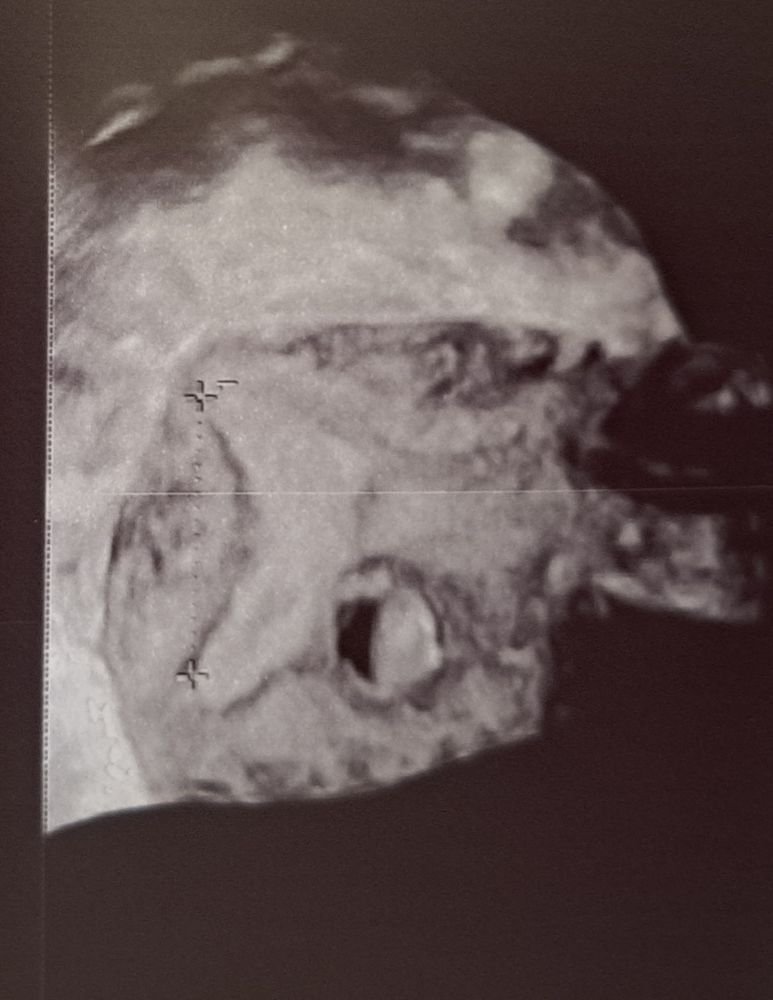

Изображение Изображение